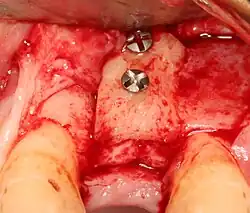

Bei größeren Knochenaufbauten wurde früher ein Rippentransplantat verwendet. Heutzutage werden monokortikale kortikospongiöse Knochenstücke aus der Beckenschaufel mittels Knochendeckelmethode entnommen, was einen zweiten Operationsbereich und eine Vollnarkose notwendig macht. Das Transplantat wird mit der spongiösen Seite auf den Kieferkamm aufgebracht und mit Osteosynthesematerial wie Miniplatten, Schrauben oder Implantaten im Kieferknochen fixiert. Mikrobewegungen der Osteoplastik müssen vollständig vermieden werden, um eine erfolgreiche Einheilung zu erreichen.